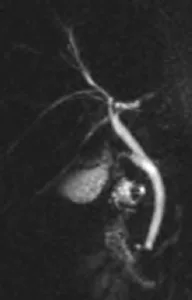

Figure 18. Mise en évidence d’une formation polypoïde (A, têtes de flèche) dans la lumière du canal hépatique commun. Cette coupe de bili-IRM montre les rapports entre le pôle supérieur de la lésion et la convergence biliaire supérieure. On note par ailleurs un abouchement variant sur le canal hépatique gauche du canal sectoriel postérieur droit (flèche). L’hypersignal tissulaire en T2 de la lésion (B) et son rehaussement en T1 après injection de gadolinium (C) montrent qu’il s’agit d’une tumeur et non d’un simple calcul ou d’un conglomérat de sludge. L’analyse de la pièce de résection chirurgicale a retrouvé un adénome tubulo-villeux de 2,5 cm de grand axe, dégénéré sous la forme d’un adénocarcinome bien différencié de type biliaire